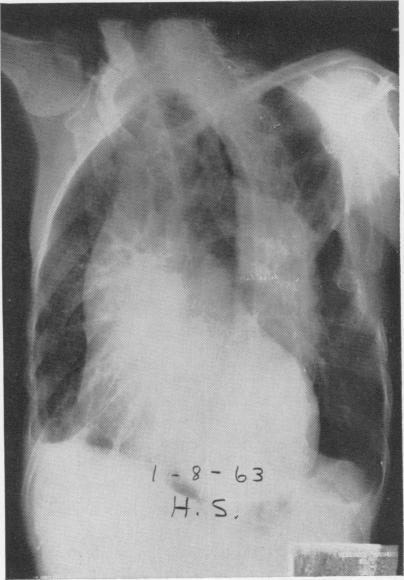

THE SURGICAL TREATMENT OF DISSECTING ANEURYSM OF THE ASCENDING AORTA: WITH A REPORT OF FOUR CASES IN THE CHRONIC STAGE.

Ann Surg. 1964 Jun;159(6):829-45. doi: 10.1097/00000658-196406000-00002.